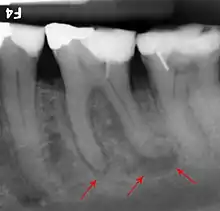

Apical periodontitis is acute or chronic inflammation around the apex of a tooth caused by an immune response to bacteria within an infected pulp.[20] It does not occur because of pulp necrosis, meaning that a tooth that tests as if it's alive (vital) may cause apical periodontitis, and a pulp which has become non-vital due to a sterile, non-infectious processes (such as trauma) may not cause any apical periodontitis.[10]:225 Bacterial cytotoxins reach the region around the roots of the tooth via the apical foramina and lateral canals, causing vasodilation, sensitization of nerves, osteolysis (bone resorption) and potentially abscess or cyst formation.[10]:228

The periodontal ligament becomes inflamed and there may be pain when biting or tapping on the tooth. On an X-ray, bone resporption appears as a radiolucent area around the end of the root, although this does not manifest immediately.[10]:228 Acute apical periodontitis is characterized by well-localized, spontaneous, persistent, moderate to severe pain.[6]:125–135 The alveolar process may be tender to palpation over the roots. The tooth may be raised in the socket and feel more prominent than the adjacent teeth.[6]:125–135